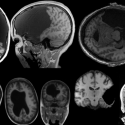

A Wearable Brain-Stimulation Device

03/22/21 Designing a wearable device to study brain function and dysfunction, with a goal of precise therapeutic interventions to treat neurodegenerative diseases Shawn Kelly

New Ways of Imaging the Brain

08/16/18 A visit to the Alan Jasanoff Lab at MIT to learn how brain scientists are developing new techniques and devices to improve brain imaging.